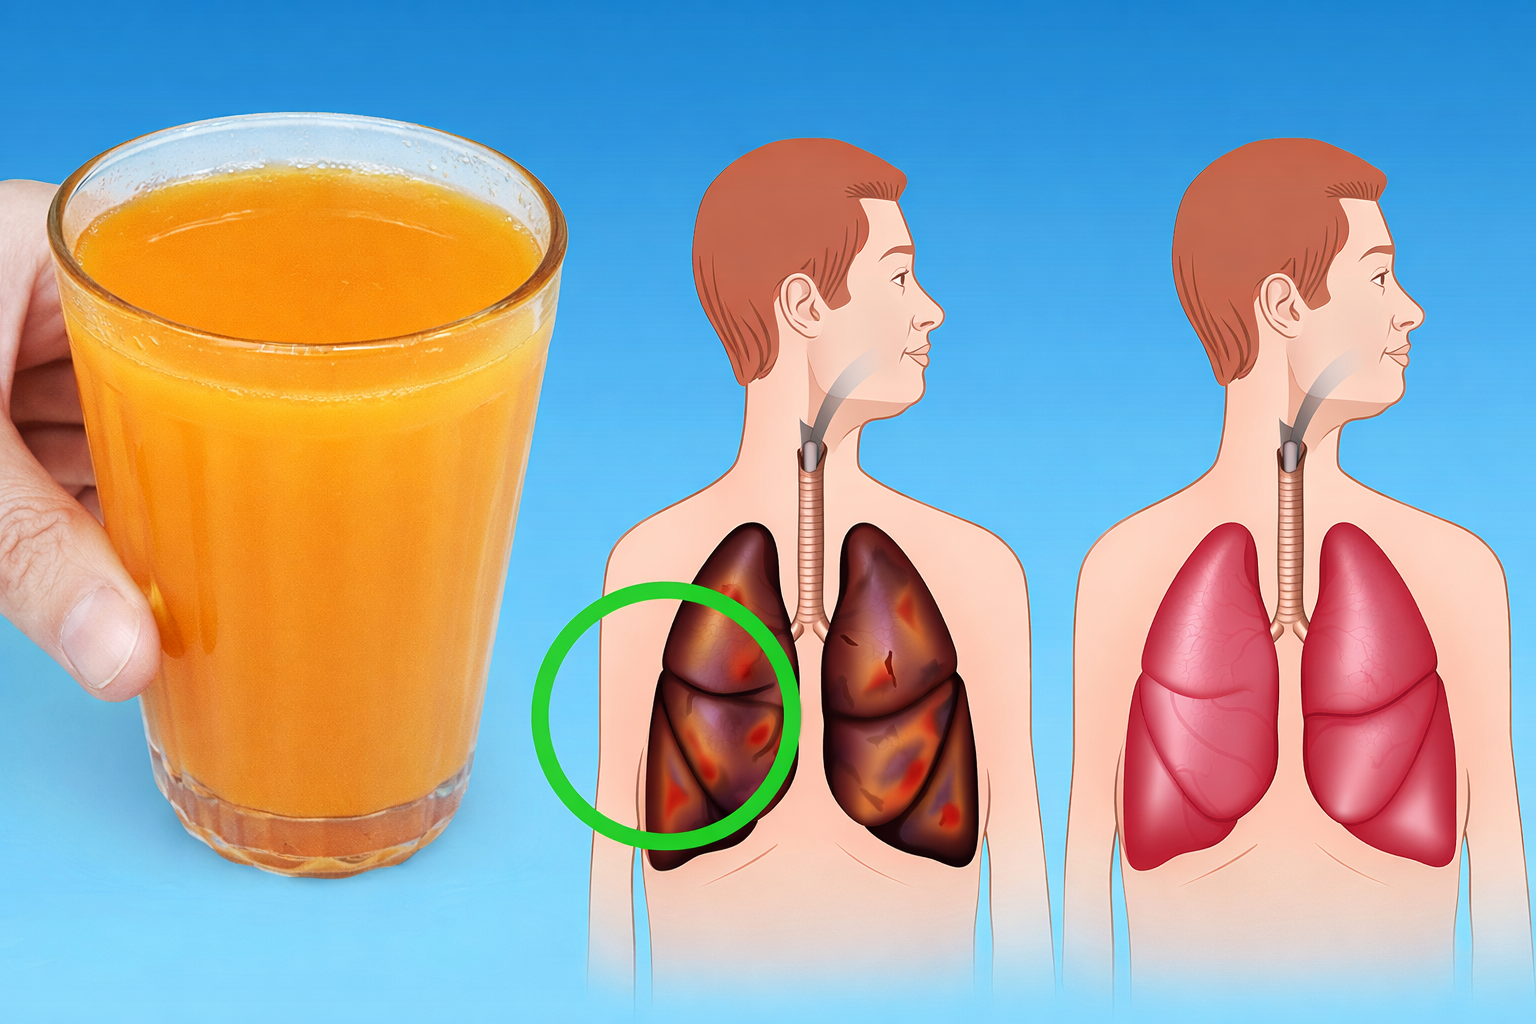

La salud de tus pulmones es más importante de lo que crees. En un entorno lleno de contaminantes y hábitos poco saludables, es fácil pasar por alto señales que pueden estar dañando tu bienestar respiratorio. Aquí descubrirás métodos sorprendentes para limpiar tus pulmones y mejorar tu respiración de manera natural.

Los pulmones son esenciales para nuestra vida, pero a menudo los descuidamos. Mantenerlos saludables no solo mejora tu capacidad respiratoria, sino que también impacta tu salud general. Ignorar síntomas como la congestión o la acumulación de mucosidad puede llevar a complicaciones serias. Aquí te mostramos cómo cuidarlos mejor.